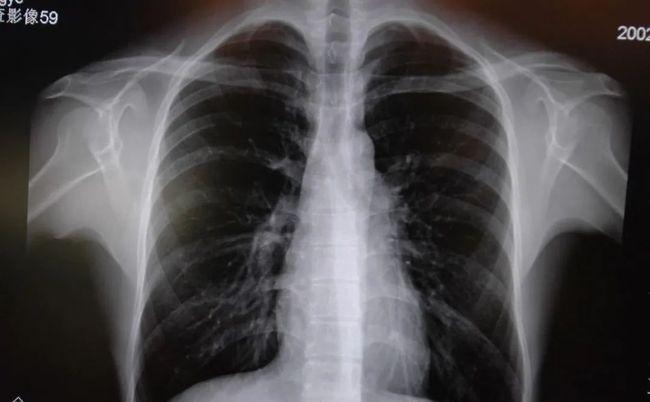

肺部有阴影是什么原因,肺部有阴影CT

肺部有阴影CT

肺部有阴影

肺部阴影诊断

肺部阴影有几种可能

肺部阴影

肺部阴影片子

新冠肺部阴影

肺部阴影图片

肺部阴影图片胸片

肺部阴影x光片